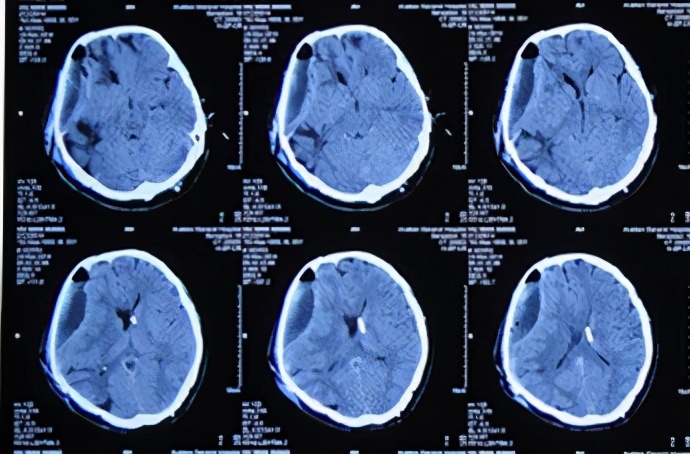

但在拔除术区硬膜外引流管后的2天,患者开始出现嗜睡加重表现。于2014年3月6日即拔除术区硬膜外引流管第3天即颅骨修补术后第9天(开颅术后第172天),再次复查头CT:硬膜外积液(血)增多,中线结构受压移位加重(图-24)。此时患者尚可唤醒,生命征平稳,遂给予继续观察。

图-24:2014年3月6日头CT

2014年3月9日即继续观察3天后即拔除术区硬膜外引流管第6天即颅骨修补术后第12天(开颅术后第175天),患者出现嗜睡状态较前加重(呼喊无应答)并伴双侧瞳孔不等大,夜间复查头颅CT:右侧硬膜外积液较前增大伴中线左侧偏移(图-25),给予甘露醇250ml静脉点滴后意识稍改善,可唤醒。

图-25:2014年3月9日头CT

2014年3月16日即留置硬膜外积液持续引流第6天即颅骨修补术后第19天(开颅术后第182天),复查头颅CT:硬膜外积气、液及血均较前缩小,中线受压移位减轻(图-27)。

图-27:2014年3月16日头CT

2014年3月24日即留置硬膜外积液持续引流第14天即颅骨修补术后第27天(开颅术后第190天),复查头CT:硬膜外积液及中线移位均再次减轻(图-28)。并在此次复查CT后拔除硬膜外引流管,继续给予静脉抗感染治疗。

图-28:2014年3月24日头CT